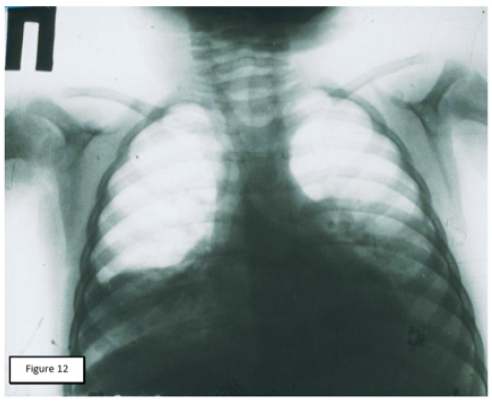

The information presented and its interpretation were incorporated as an integral part of the new АP doctrine and served as a justification for the subsequent revision of the treatment principles for this group of patients. New pathogenetic approaches in treatment were used in 101 patients with signs of infiltrative changes in the lungs. Another 102 patients treated according to the revised principles had a pleural reaction at the time of admission. The final results allowed to speak about the possibility of guaranteed prevention of complications of АP. The use of pathogenetic approaches to treatment in the initial stage of the so-called “toxic” forms of AP ( CVB , СupТ, cold wraps of patients, intensive restoration of bronchial patency, rejection of intravenous infusions , intramuscular or intravenous administration of antibiotics with a minimum volume of solution) showed that in comparison with the same group who received the previous first aid complex, the number of pleuro-pulmonary complications is significantly reduced (in the group of patients who did not have a pleural response at admission ,101 patients, T = 8.65; P < 0.001), the length of stay in the hospital decreased by three times, respectively, material and financial costs of treatment were significantly reduced, there were no deaths. A detailed description of the whole complex of works was first published in Russian [7], and last year-in English [8]. One of our observations can serve as an illustration of new approaches in the treatment of patients with AР (Figure 7 & 8).

Figure 8: X-ray photograph of the same patient (see Figure 7) five days following the clinical treatment (CVB, antibiotic therapy, bronchus-draining therapy, including lavages through microtracheostoma). Full recovery of airiness in both lungs.